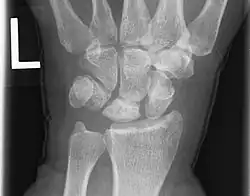

La maladie de Kienböck est une pathologie du lunatum, os central de la rangée proximale du carpe, qui peut aboutir à sa fracture et à son écrasement. Cela occasionne douleur, raideur, et progressivement dégradation du reste du poignet.

Sur les formes plus évoluées, la radiographie permet le diagnostic de la maladie. Les anomalies radiographiques sont regroupées dans la classification de Lichtman[6] qui reflète l'évolution de la maladie :

- Stade I : radiographie normale.

- Stade II : augmentation de la densité du lunatum.

- Stade IIIa : aplatissement du lunatum (de profil confirmé par une anomalie de l'index de Stahl).

- Stade IIIb : aplatissement du lunatum et bascule palmaire du scaphoïde (de profil confirmé par une anomalie de l'angle radio-scaphoïdien).

- Stade IIIc : Fracture du lunatum.

- Stade IV : arthrose intra-carpienne ou radio-carpienne (Kienböck's Disease Advanced Collapse : KDAC) .